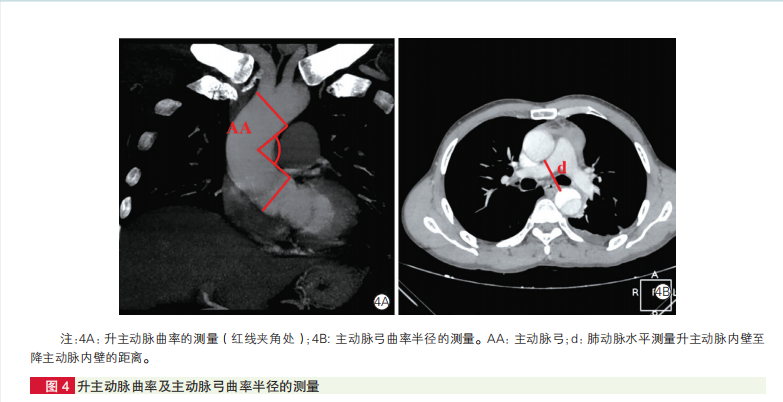

昆明医科大学第二附属医院王家平等研究也显示,B型主动脉夹层患者的主动脉形态与无主动脉疾病人群有差异,其中左锁骨下动脉(LSA)根部直径、主动脉弓宽度、升主动脉曲率、主动脉弓曲率半径以及主动脉弓局部扭转度与B型主动脉夹层发生相关。

B型主动脉夹层组主动脉弓宽度及高度均较对照组增大,升主动脉曲率小于对照组,主动脉弓曲率半径大于对照组。

多因素Logistic回归分析显示,LSA根部直径增大、主动脉弓宽度增大、升主动脉曲率减小、主动脉弓曲率半径增大、主动脉弓局部扭转度增大与B型主动脉夹层的发生独立相关。